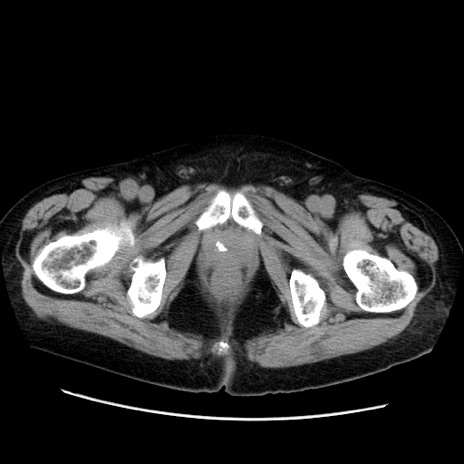

症例21(横断像)

【症例】70歳代男性

【主訴】腹痛

【現病歴】肝硬変・肝細胞癌にてかかりつけの方。約9時間前に食後より腹痛出現。症状が徐々に増悪し、嘔吐出現したため来院。

【既往歴】肝硬変、肝細胞癌(RFA、TACE後)

【身体所見】意識清明、表情苦悶様、BT 36℃、BP 129/78mmHg、P 88bpm、SpO2 97%(RA)、右上腹部から心窩部にかけて圧痛あり、反跳痛なし、筋性防御あり。

【データ】WBC 5800、CRP 0.16